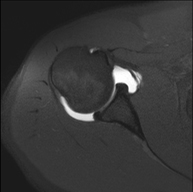

- RM Hombro

Exploración para el estudio de lesiones en tendones, músculos y articulación. Su principal utilidad reside en diagnosticar las lesiones de los tendones del manguito rotador. Tiene una duración aproximada de 20 minutos. No emplea radiación ionizante. - RM Brazo

Exploración para el estudio de las lesiones en pequeñas estructuras anatómicas de la articulación que suelen lesionarse en pacientes que sufren luxación o inestabilidad crónica. El estudio viene precedido por una inyección de contraste en el interior de la articulación, realizada bajo control de rayos X. La duración global de los dos procedimientos es de 50 minutos. - Artro-RM Muñeca